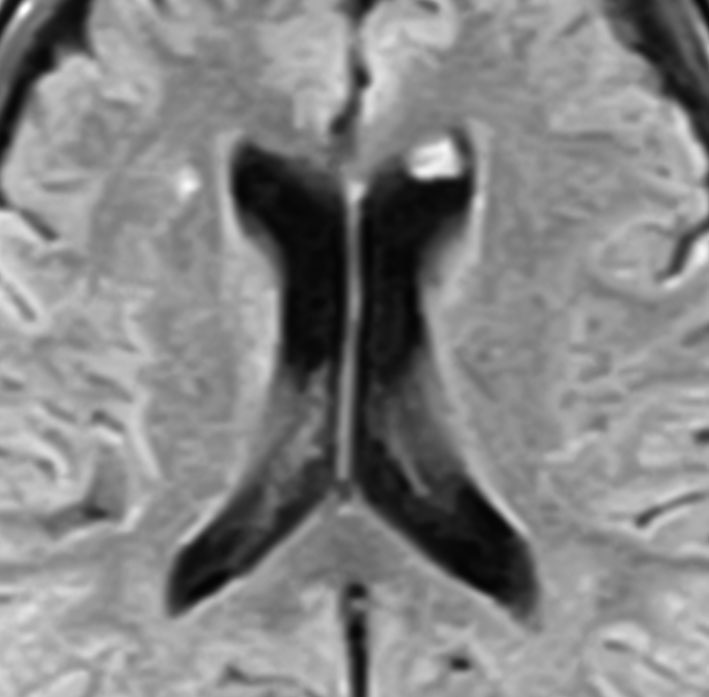

よくみつかる典型的な例です

中年男性に偶然発見された15mmくらいの上衣下腫です。側脳室前角の壁にピッタリくっつくようにキノコのように生えています。下の2枚はガドリニウム造影ですが増強されないのが特徴です。この点で中枢性神経細胞腫 central neurocytomaと区別できます。中枢性神経細胞腫はゆっくりですが大きくなる腫瘍です。でもこのような上衣下腫は大きくなるのはとてもまれです。小さいし水頭症にもならないので,なにも治療しないでほっておきます。間違っても開頭手術などしません。